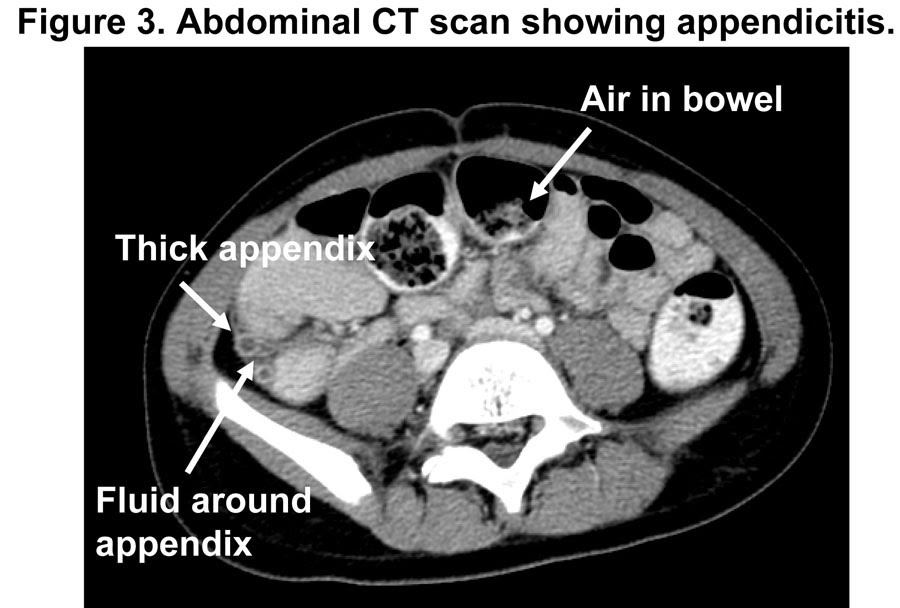

CT Evaluation of Appendicitis and Its Complications Imaging Techniques Turbid Fluid Appendicitis — larger quantities of fluid, especially if circumscribed and/or turbid, often accompanied by local or generalized paralytic ileus are. For diagnosing acute appendicitis, both ruling in and ruling out. It is a very common condition in general. — acute appendicitis is the most common abdominal surgical emergency in the world, with a lifetime risk of 8.6. —. Turbid Fluid Appendicitis.